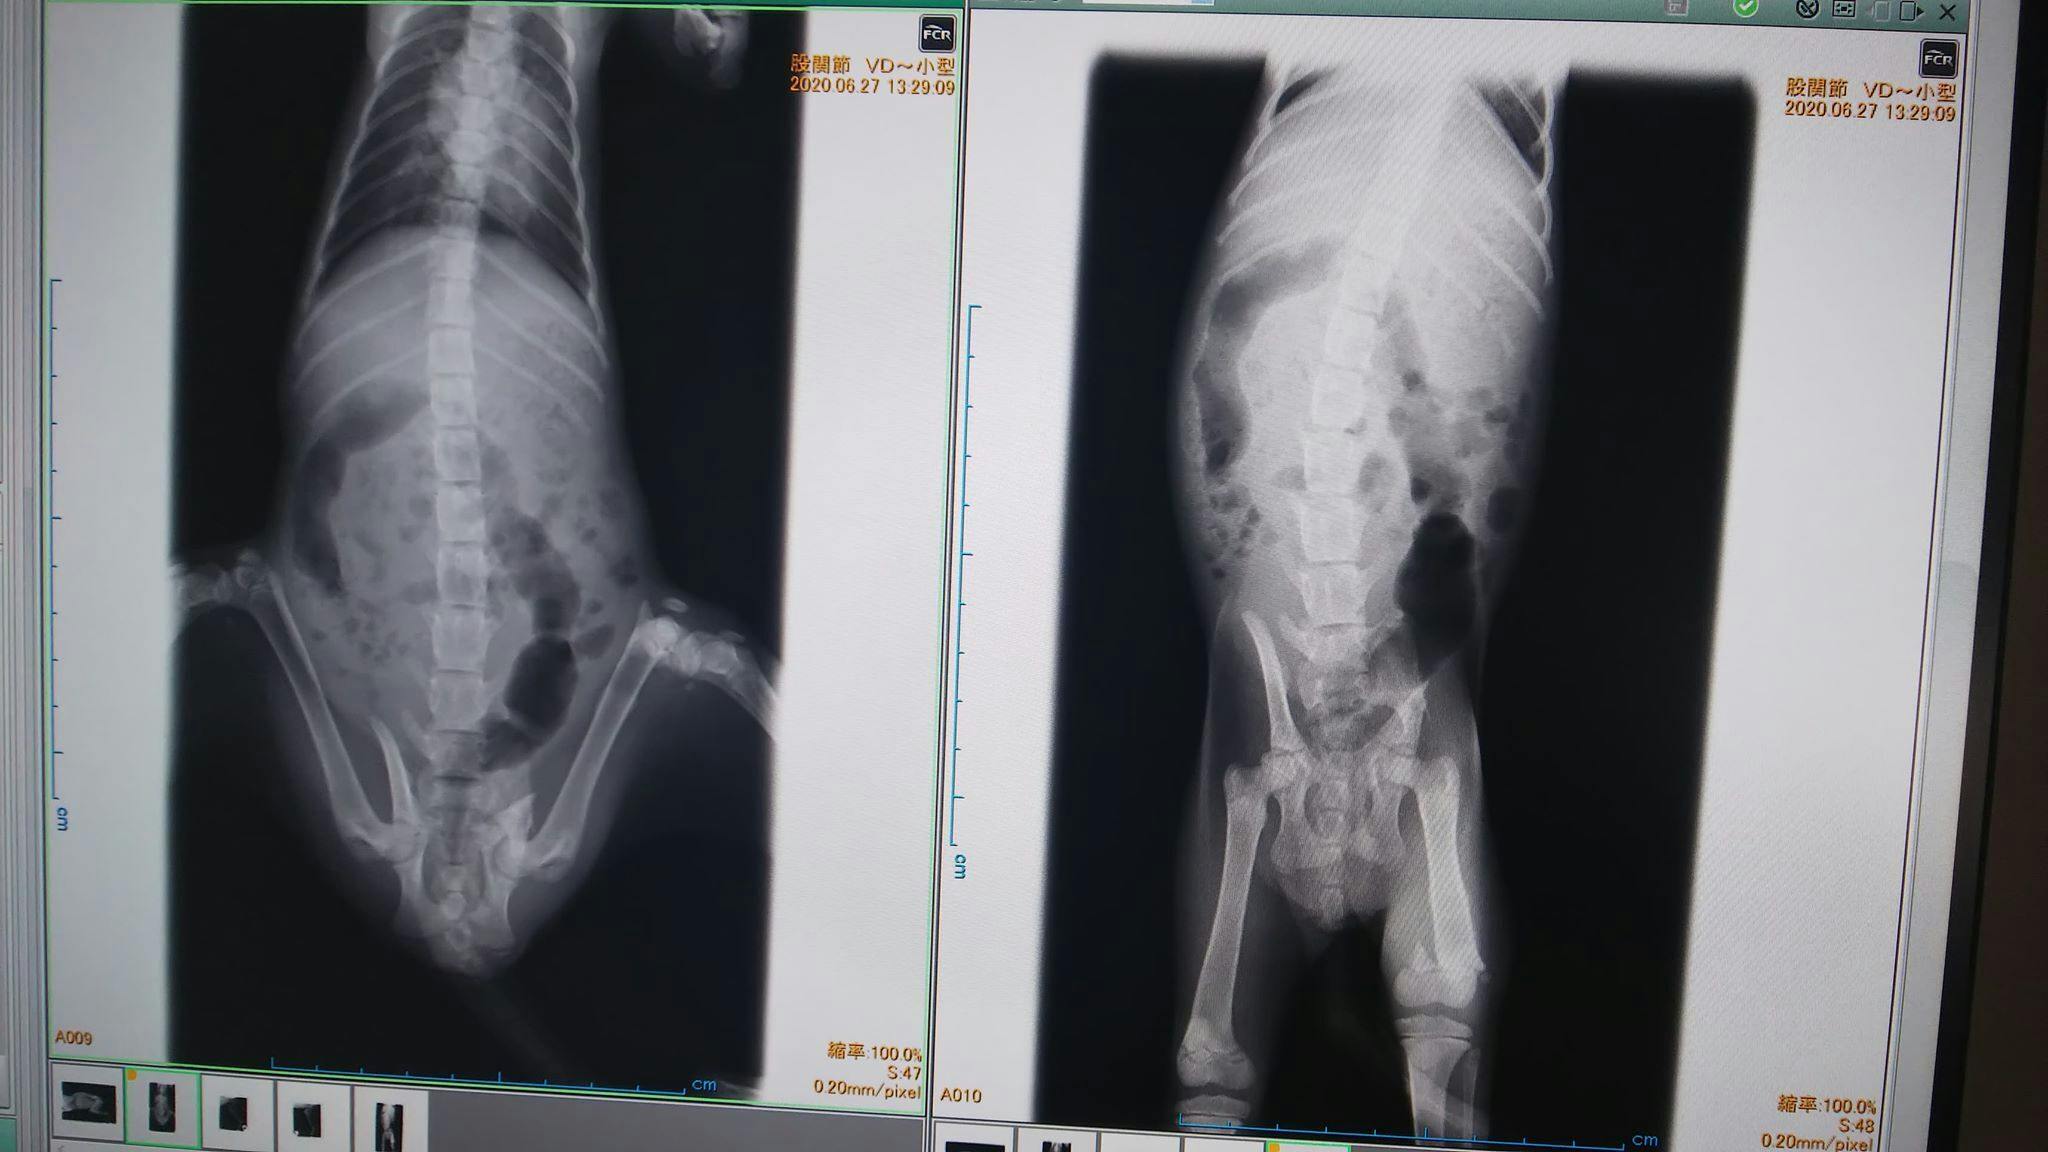

保護してそのまま近所の病院でレントゲンしたところ骨折7箇所でした。

骨盤脱臼、左右腸骨、尾てい骨、大腿骨関節付近、尾の7箇所骨折と内出血。

内蔵軽症損傷、血便。

ほぼ同じような形になるので借りてきた画像で説明します。